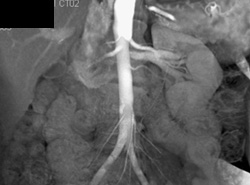

Normal CT Urogram